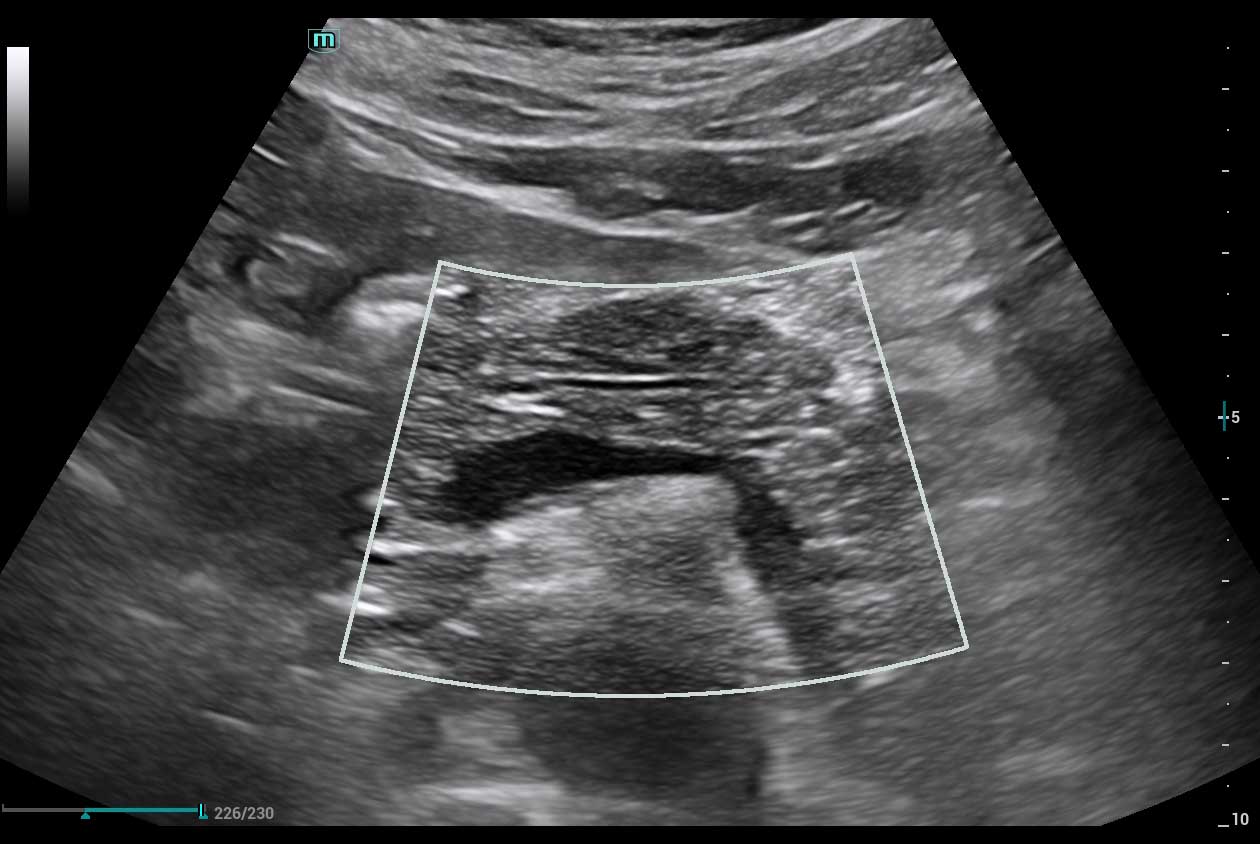

Clinical Images